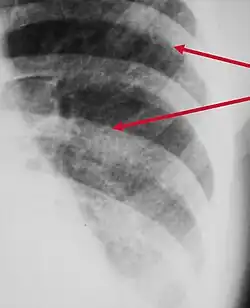

Peribronchial cuffing

Peribronchial cuffing, also referred to as peribronchial thickening or bronchial wall thickening, is a radiologic sign which occurs when excess fluid or mucus buildup in the small airway passages of the lung causes localized patches of atelectasis (lung collapse).[1] This causes the area around the bronchus to appear more prominent on an X-ray. It has also been described as donut sign, considering the edge is thicker, and the center contains air.